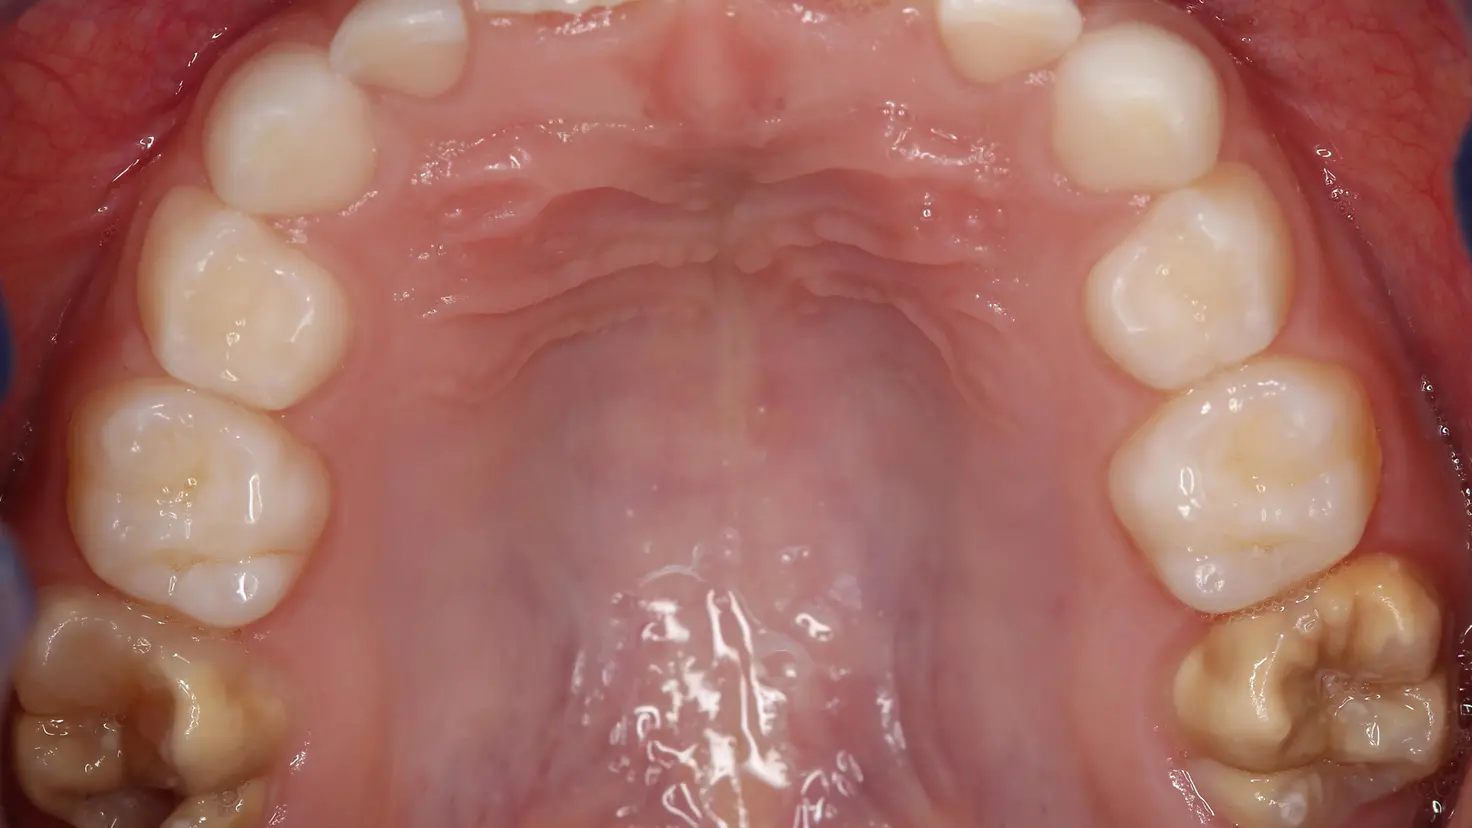

Kariesfreies Gebiss eines 7-jährigen Patienten mit MIH an beiden oberen ersten Backenzähen.

Kariesfreies Gebiss eines 7-jährigen Patienten mit MIH an beiden oberen ersten Backenzähen. Foto: Prof. Dr. Katrin Bekes, MME Wien/DGZMK

Im Fachjargon werden Kreidezähne als Molaren-Inzisiven-Hypomineralisation (MIH) beschrieben, da die Schmelzstörung typischerweise an den ersten bleibenden Backenzähnen (Molaren) und bleibenden Schneidezähnen vorkommt. Laut Barmer Zahnreport variiert das Auftreten von Kreidezähnen regional sehr stark voneinander. So liegt die Betroffenenrate bei den Sechs- bis Neunjährigen in Mecklenburg-Vorpommern mit 8,2 Prozent nur leicht über dem Bundesniveau von 8 Prozent. Die niedrigste Rate hat Hamburg mit 5,5 Prozent und Nordrhein-Westfalen die höchste mit 10,2 Prozent. Auch auf Kreisebene gibt es große Unterschiede: In Rostock sind 10,4 Prozent der Kinder der Altersgruppe von Kreidezähnen betroffen, in Schwerin 9,4 Prozent. In Vorpommern-Greifswald ist die Betroffenenrate mit 6,2 Prozent die landesweit niedrigste. „Diese regionalen Unterschiede können wir nicht erklären“, sagt Henning Kutzbach.